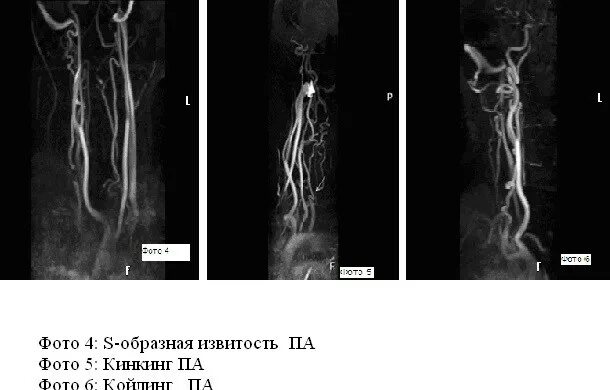

С образная извитость артерий